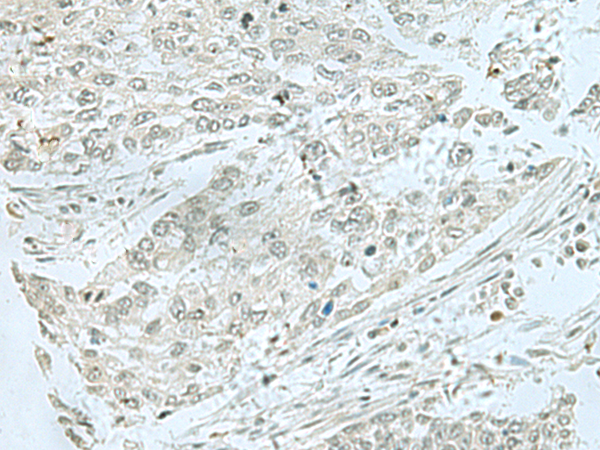

分类: 科研抗体货号: P10049别名: C1orf83应用: IHC反应种属: Human, Mouse, Rat